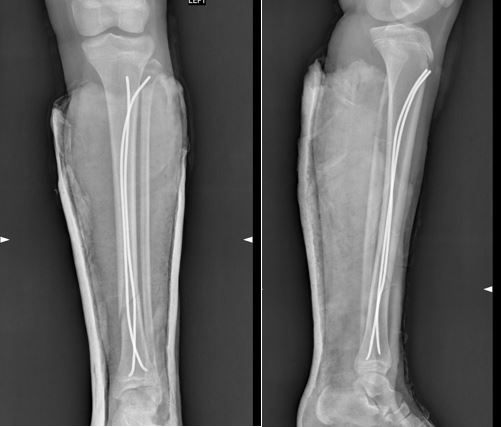

Фиксация титановыми эластичными стержнями - это современный метод лечения, при котором через небольшие хирургические доступы внутрь кости вводят тонкие гибкие стержни из титана. Благодаря конструкции и правильной технике имплантации они удерживают отломки в правильном положении, пока кость срастается.

Вот так это выглядит на рентгеновских изображениях: